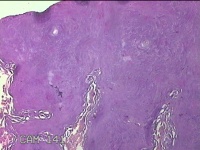

左腕掌侧结节

性别

男

年龄

57岁

临床诊断

皮下结节

一般病史

近3个月来,发现左腕掌侧一结节,无明显疼痛及不适。

标本名称

大体所见

灰白暗红色皮肤样结节1.5x0.8x0.3cm一个,表面糜烂,切面灰白暗红色,质软。

良性病变。